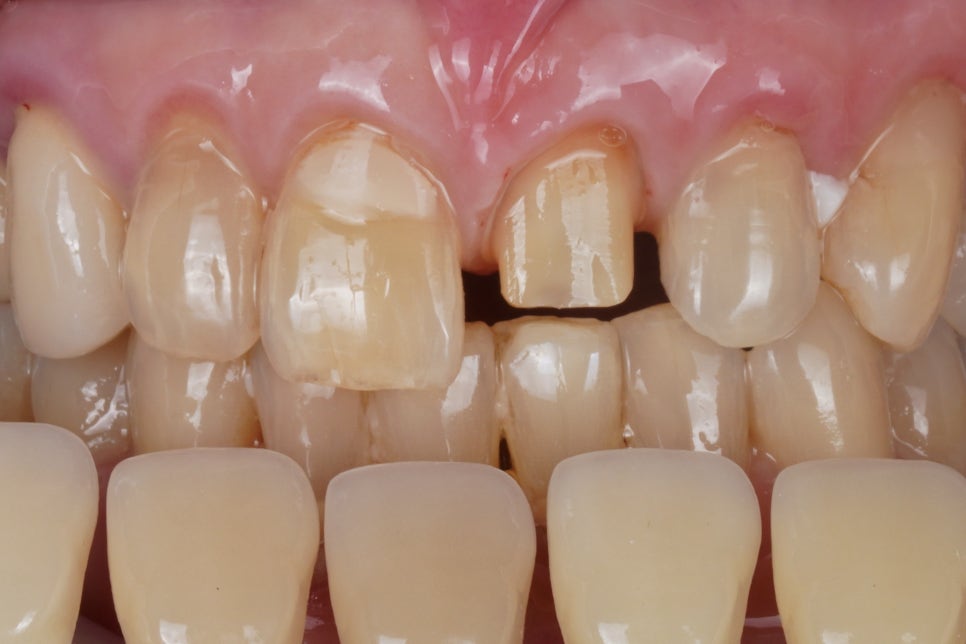

잘 된 신경치료

그렇게 긴 시간 동안

계속해서 지켜보았지만

불편감이 계속 있고

점점 치아 상태가 안 좋아져서

신경치료를 하게 되었습니다.

신경관이 석회화가 많이 돼서

돌처럼 굳어있었기 때문에

신경치료 자체도 쉽지는 않았는데요,

다행히 치아 구조 손실을 최소화하고

신경관을 잘 찾아서

신경치료를 마무리할 수 있었습니다.

신경치료가 마무리된 뒤에는

치아를 온전히 보호하기 위해

치아를 깎아 크라운을 씌우게 됩니다.

이 환자분께서는

앞니끼리 좀 깊게 물리는 편이었는데요,

앞니가 이미 마모가 많이 되어서

불안한 면이 있었고,

아랫니가 자꾸 넘어진 앞니를 때리면서

불편감이 지속되고 있었기 때문에

크라운 치료하기 위해

치아를 깎을 때

그 점을 굉장히 신경 써야 했습니다.